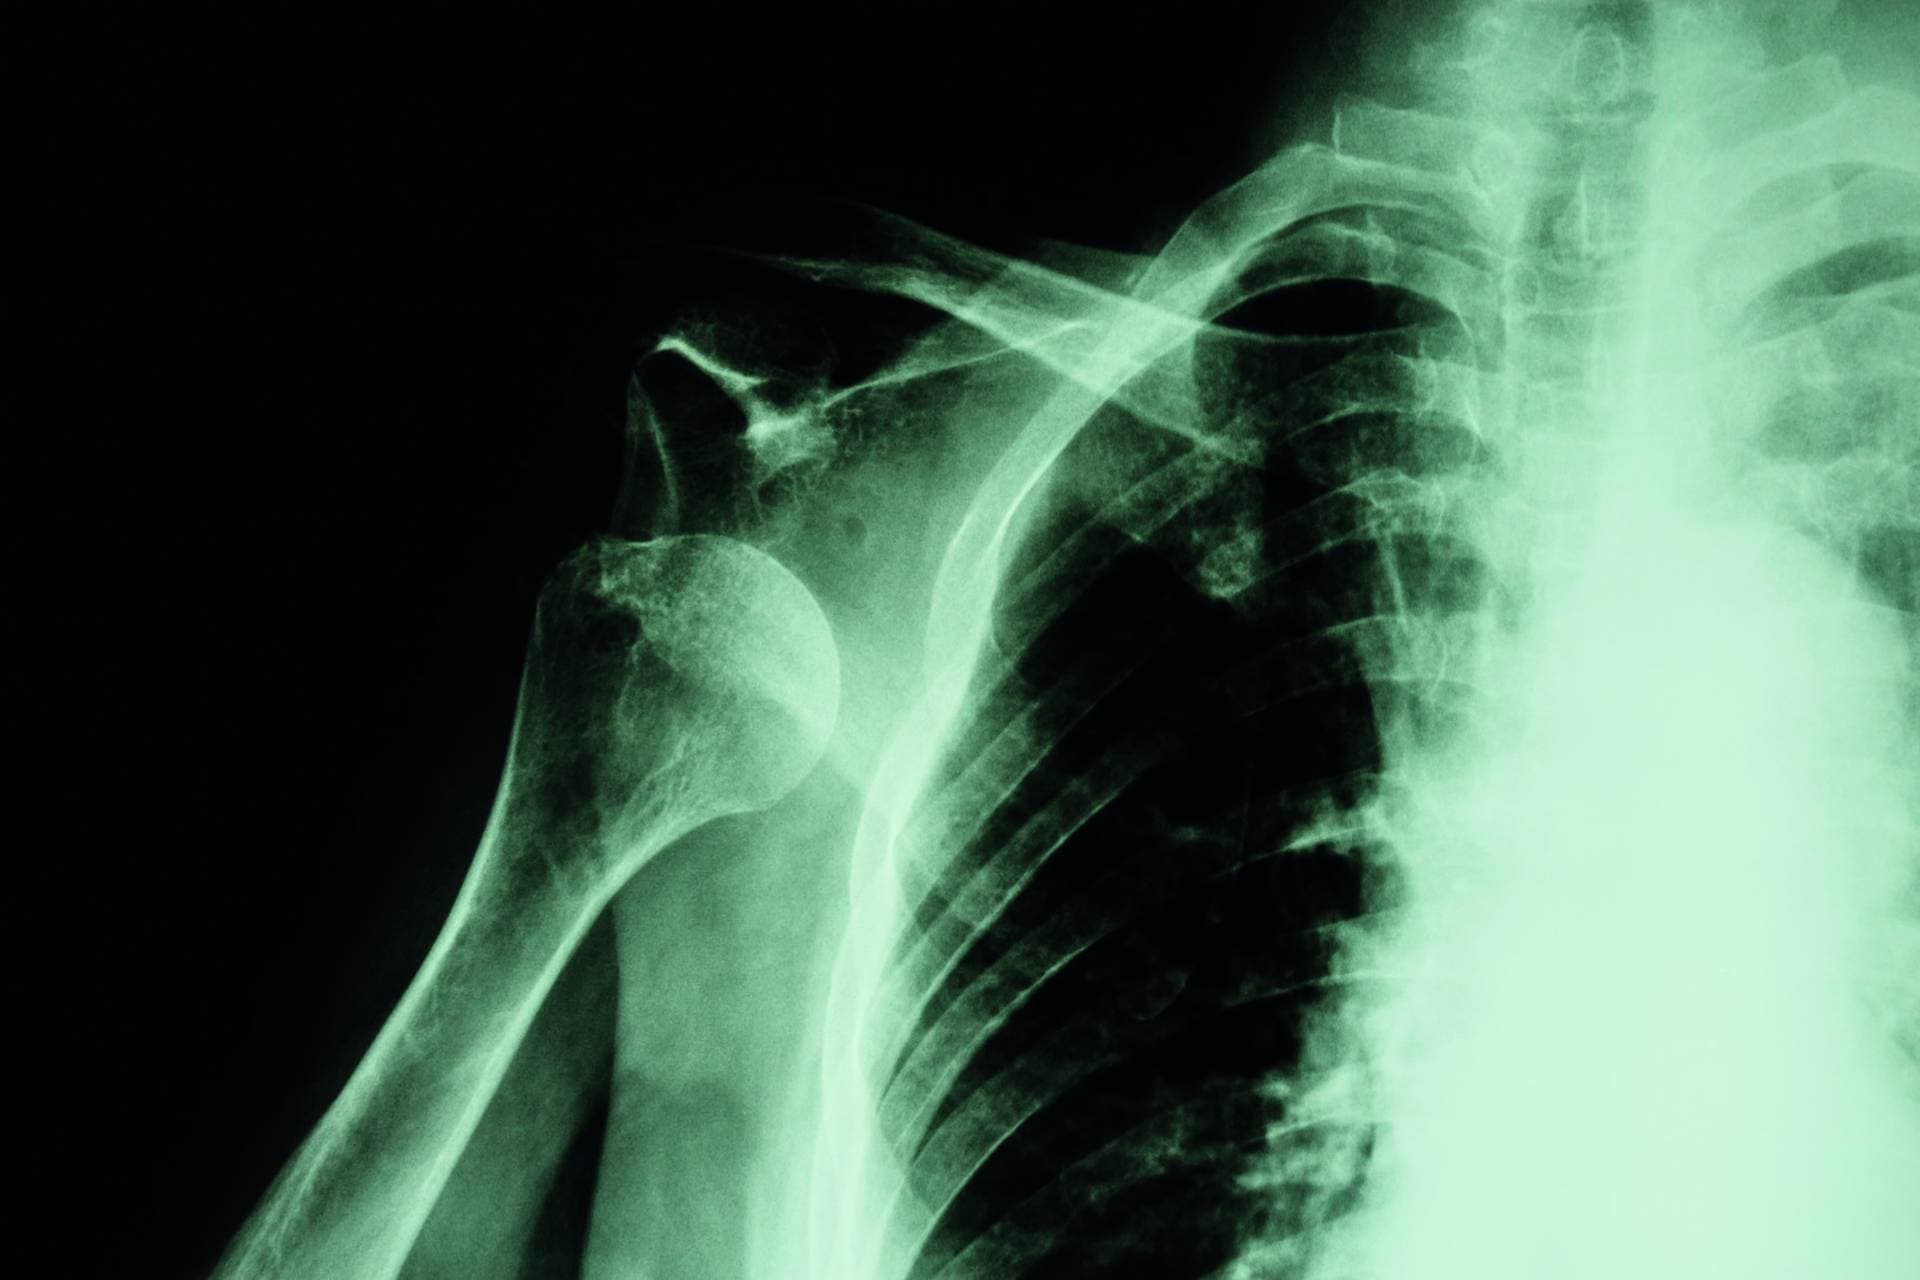

Mit einem Anteil von mehr als 95% dominiert die anteriore Dislokation. In der Untersuchung fällt eine asymmetrische Schulterkontur mit prominentem Akromion und anteroinferior tastbarem Humeruskopf auf. Verdachtsdiagnose, Richtung der Dislokation und Begleitfrakturen der Tuberositas major lassen sich im Röntgenbild sichern (anterior-posteriore und skapulare Aufnahme).